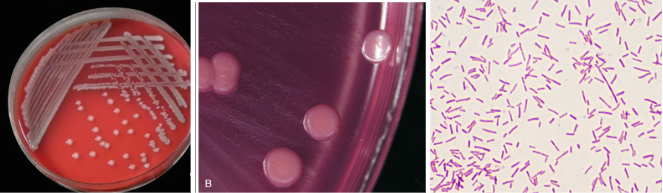

Blood Culture from 72 yr old male (immunocompromised)

Colony Morphology: 4+, small, white, NH, dry, domed

1) small GPR palisade

2) Vitek GP-ID

3) Corynebacterium sp.